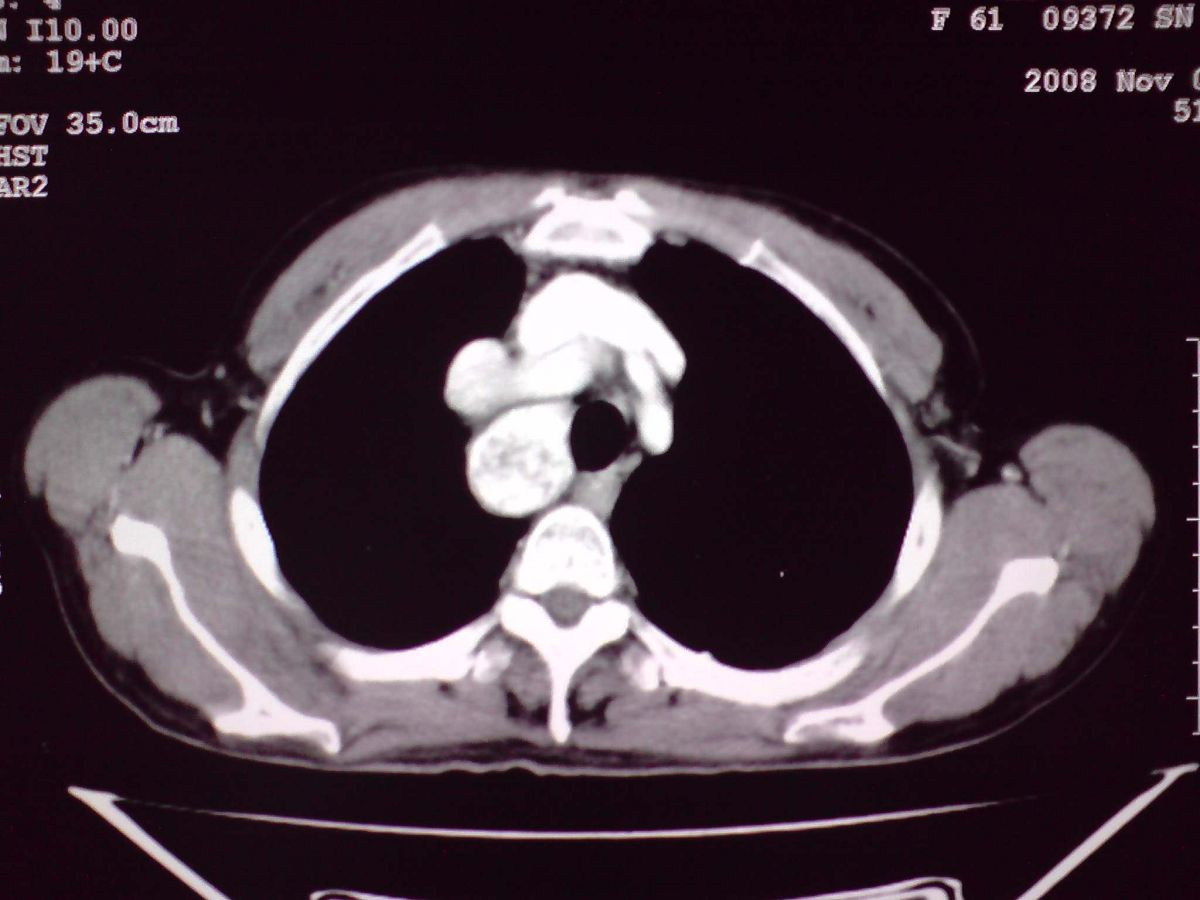

患者女性,65岁,无明显不适,甲状腺功能无异常

双侧甲状腺肿大,向下部分突入胸腔,双侧甲状腺内密度不均,可见结节状低密度影,并见散在斑点状钙化,增强后病灶实性部分强化明显,气管受压稍变窄左移。

考虑:双侧甲状腺腺瘤可能,不除外甲状腺癌。

胸内甲状腺,双侧结节状甲状腺肿伴右侧甲状腺腺瘤。

甲状腺左右叶增大,并向下突入胸腔内,其内可见多发条片状钙化影及囊性低密度影,邻近组织及血管无浸润、包埋征像,双侧结节性甲状腺肿伴右侧甲状腺腺瘤形成可能性大,甲状腺癌待排;因病人就要手术,期待结果。

我们的诊断和大家一致,但我们地区的上级医院考虑右纵隔是另外一种病变